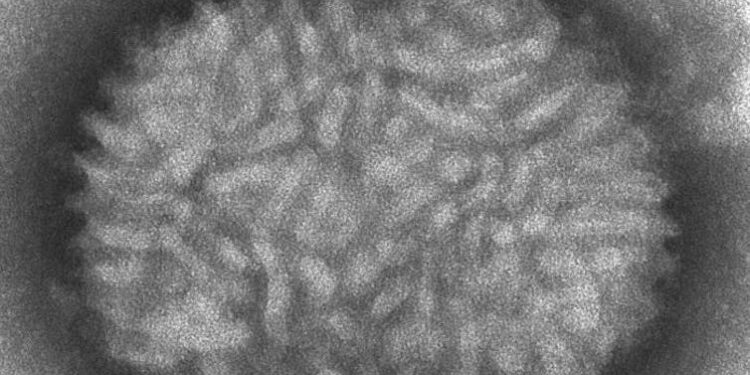

CDC/Cynthia Goldsmith